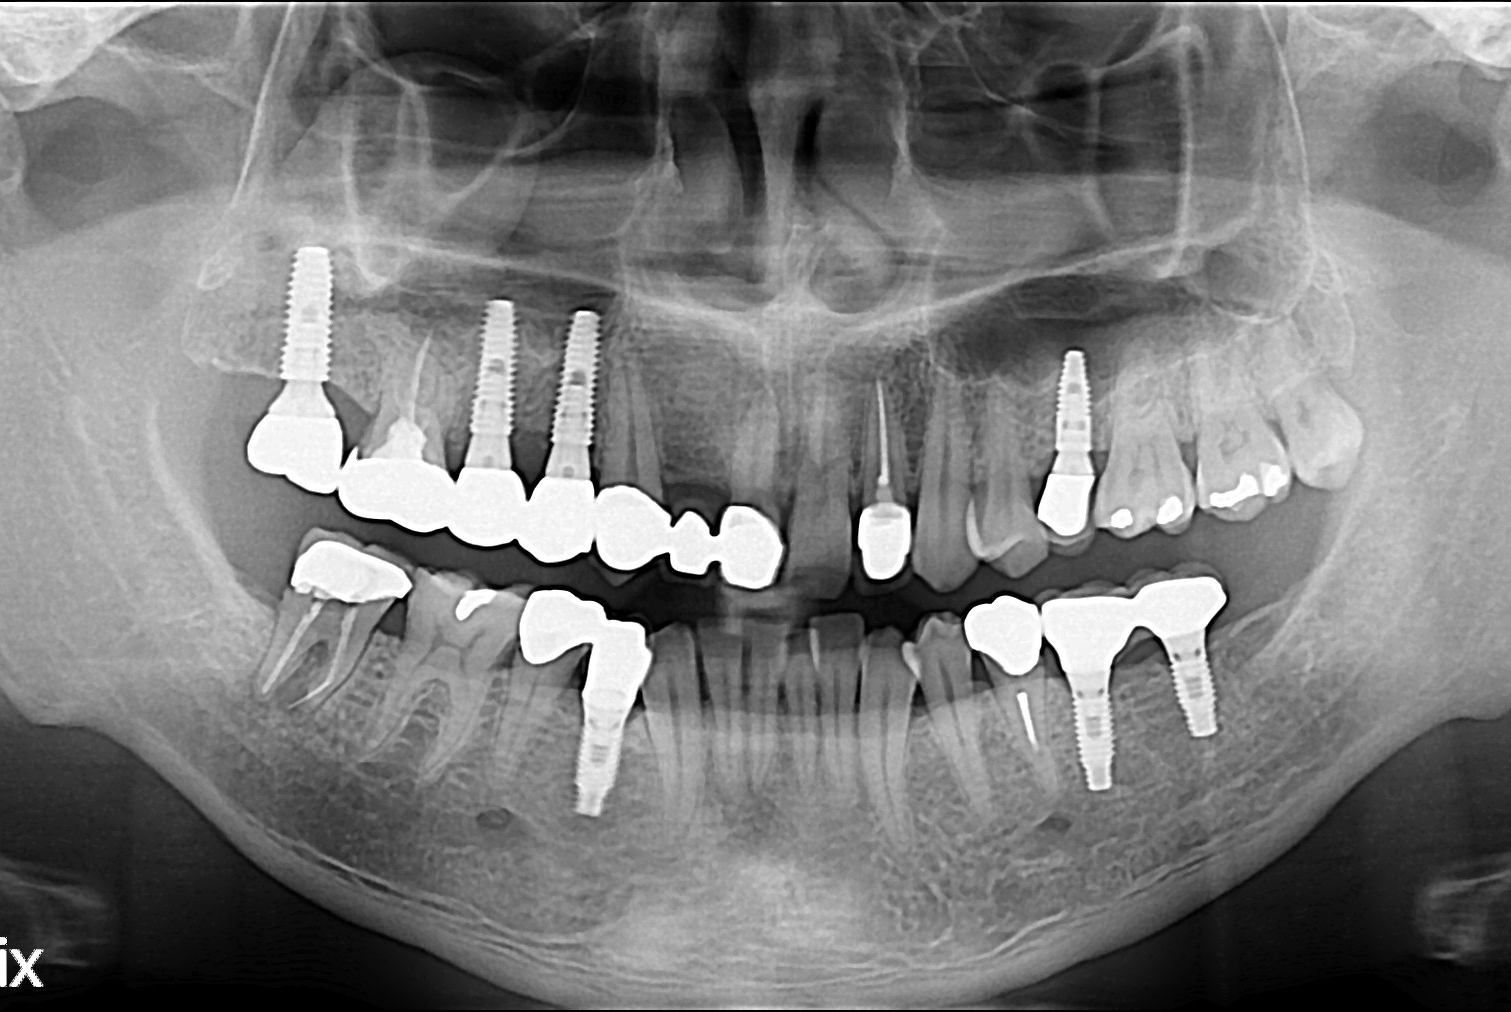

[임플란트] 임플란트

치료후 : 2017-06-01

세종치과는 많은 환자와 다양한 케이스를 바탕으로 항상 편안한 임플란트 수술을 제공하고자 노력하고,

오래동안 튼튼히 쓸 수 있는 임플란트 수술을 가장 큰 목표로 삼고 있습니다